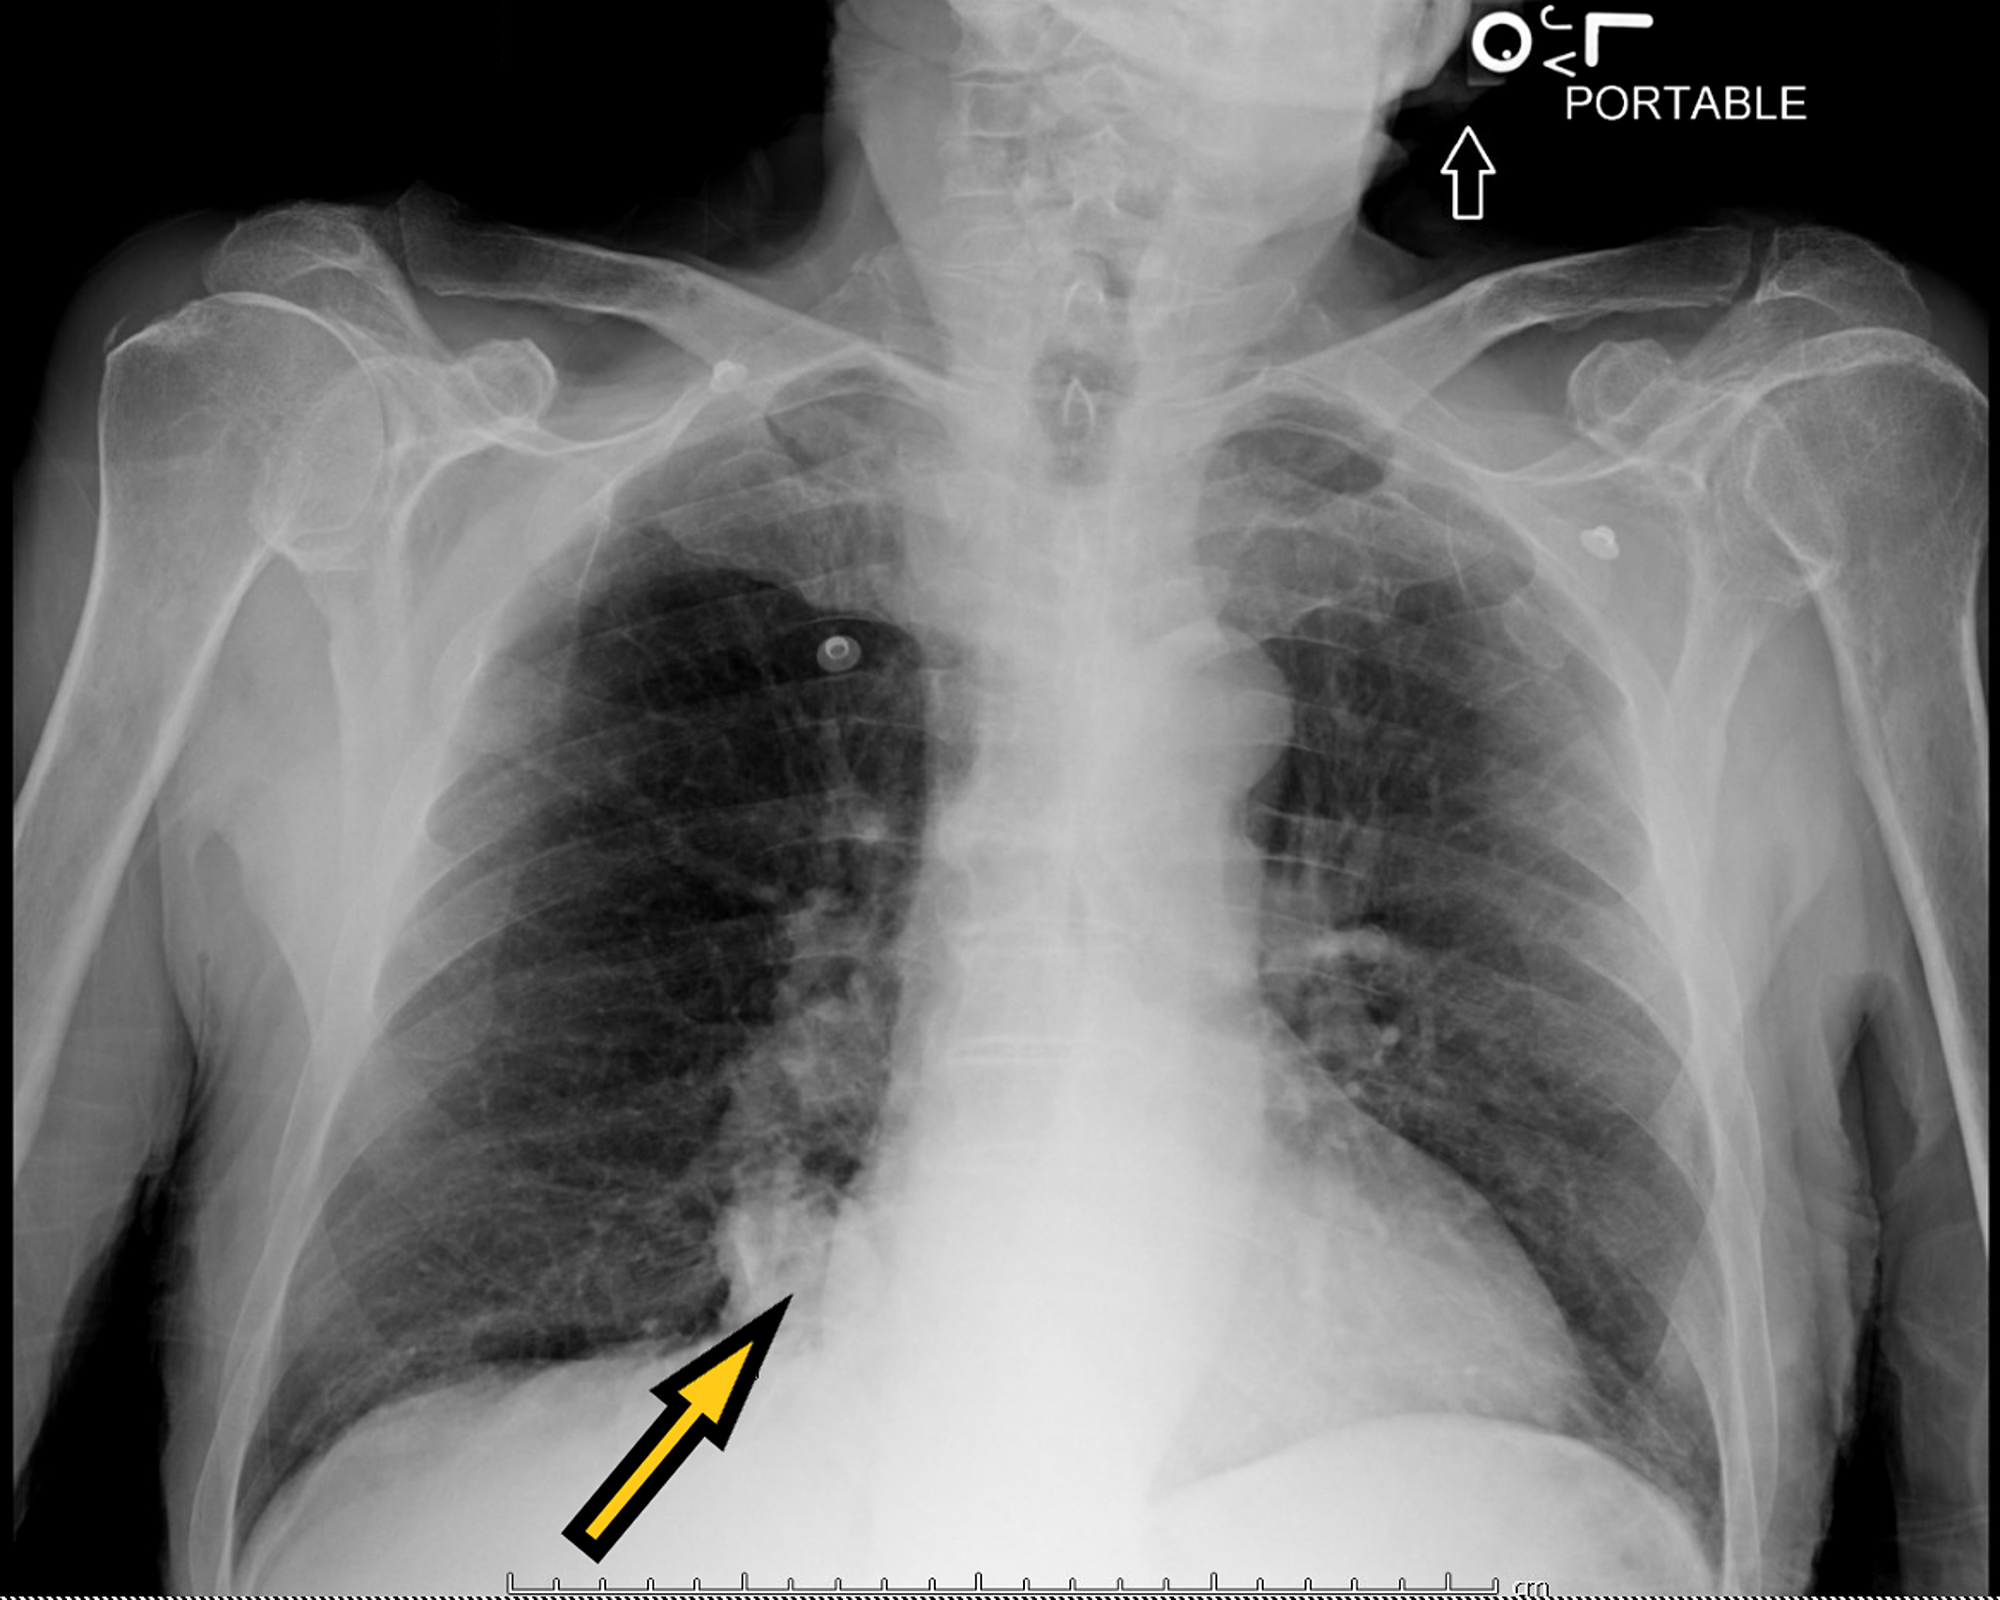

Literature review chest x ray image This image shows literature review chest x ray.

From march 15 to april 20, 2020 patients with positive reverse transcription polymerase. This is a healthy patient who came to emergency department with a clinical picture of pneumonia. Relevant studies were identified by searching pubmed/medline. Conclusion: review of the literature suggests that the lateral chest radiograph should not be performed routinely unless clinically indicated. Seventeen studies presented chest x-ray film data.